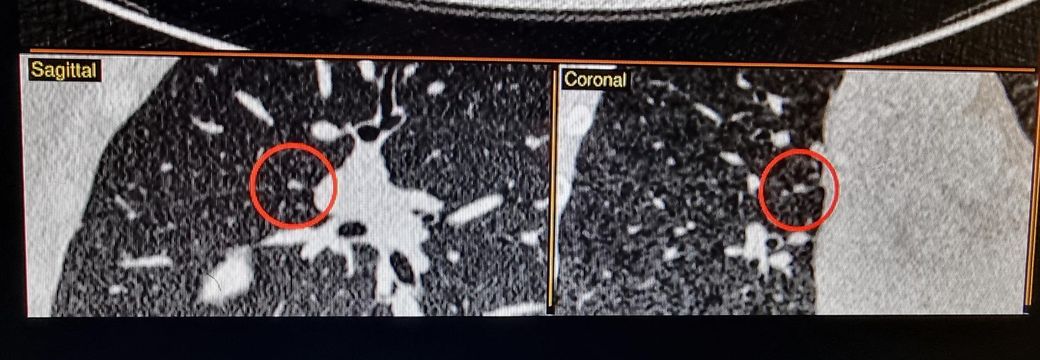

25년에 같은 저선량 CT에서 lucas라는 AI가 찾아낸 사진 2장은 빨간동그라미로 되어있습니다.*

♧ 고형 같나요 간유리 같나요?

Ai 는 우상엽 solid라는데 오늘 2차병원에서 중간위치고 간유리에 가깝다라고 들어서요

solid nodule인지 ground glass nodule인지는 clear cut하게 나누어지는 것이 아닙니다. 결절이 색이 또렷하면 solid nodule인 것이고 흐지부지하면 ground glass nodule인 것입니다. 이건 육안 소견을 두고 말하는 것입니다. 따라서 일부 nodule에 있어서는 판독하는 의사에 따라 소견이 다를 수 있습니다.